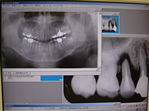

◆根管治療

むし歯等で歯の神経が死んでしまった場合に必要となる根の治療です。

根管治療X線写真